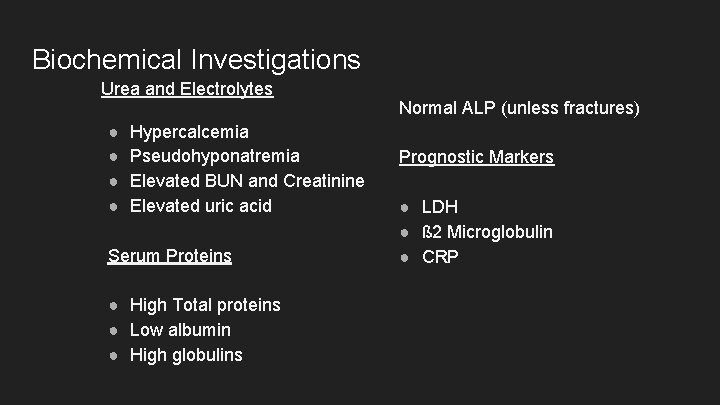

Biochemical Investigations Urea and Electrolytes ● ● Hypercalcemia Pseudohyponatremia Elevated BUN and Creatinine Elevated uric acid Serum Proteins ● High Total proteins ● Low albumin ● High globulins Normal ALP (unless fractures) Prognostic Markers ● LDH ● ß 2 Microglobulin ● CRP